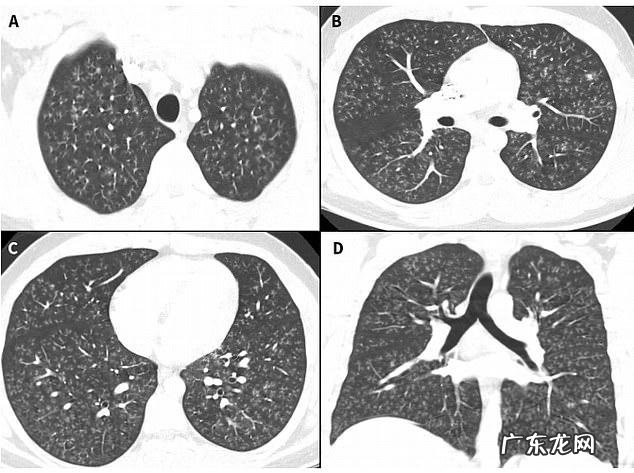

同年,多家海内外媒体报道过一名17岁加拿大少年的病例 。该少年出现剧烈咳嗽,被诊断为闭塞性细支气管炎,继而恶化为双肺衰竭,必须进行双肺移植 。影像学检查显示,其肺部“就像爆米花一样,面目全非” 。

病史分析发现,罪魁祸首就是电子烟 。该款电子烟使用调味剂双乙酰,一种常见的食用香精添加剂,可以模拟出黄油味 。但雾化后,双乙酰会增加闭塞性细支气管炎和其他严重呼吸道疾病风险 。

图2 17岁少年住院第一天的肺部影像学结果 。/Canadian Medical Association Journal